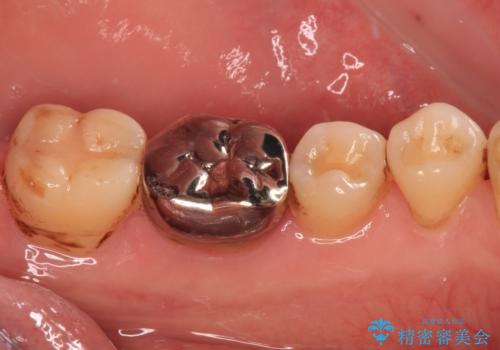

- 人と話す際に、下顎の奥にある銀歯が目立って気になるとのことで来院された患者様です。

左右の奥歯に銀歯のクラウンが装着されていたため、銀歯除去後に仮歯に置き換え、フルジルコニアクラウンにて補綴治療を行うこととしました。